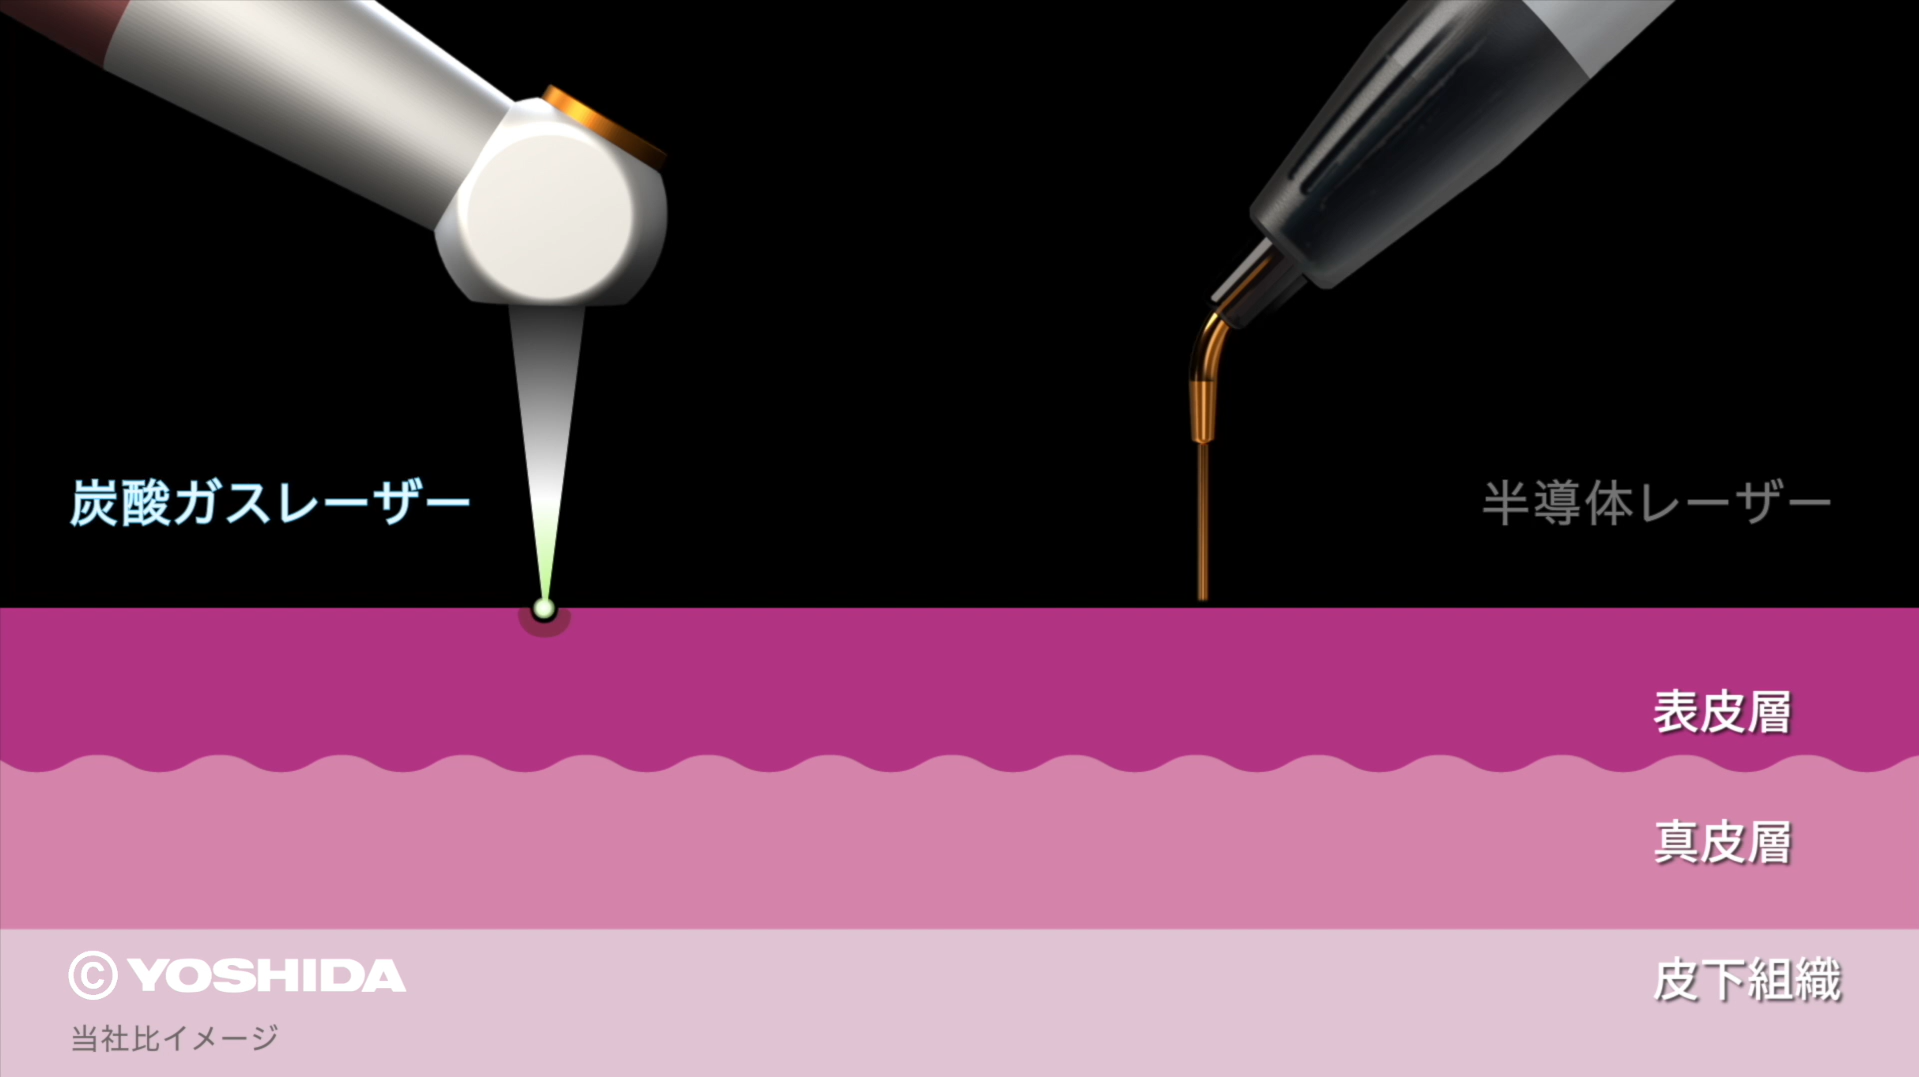

(1)オペレーザー商品とは、株式会社吉田製作所が製造する歯科用レーザー機器であって、「オペレーザー」を販売名に含む商品をいいます。